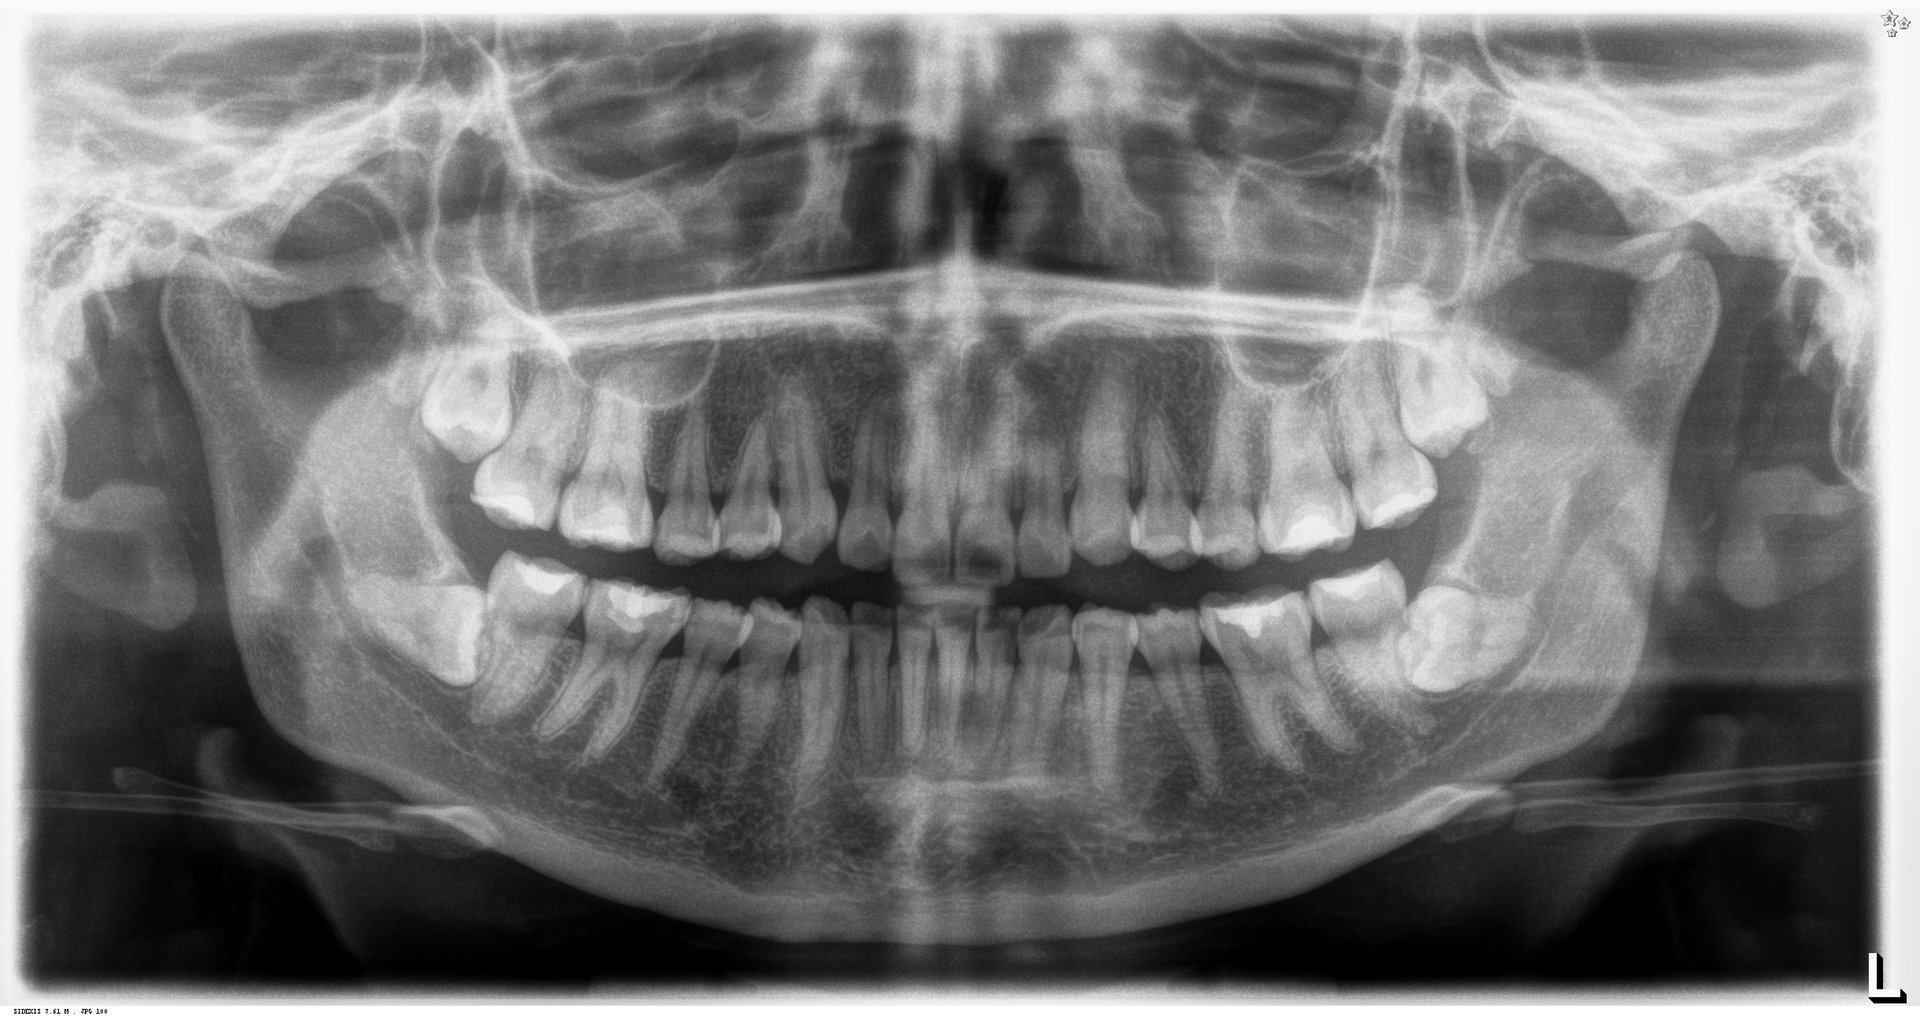

Descripción de imagen

Radiografía Panorámica

La radiografía panorámica es una herramienta esencial que ofrece una vista completa de la estructura dental y ósea, capturando todos los dientes, maxilar, mandíbula y las estructuras circundantes en una sola imagen.